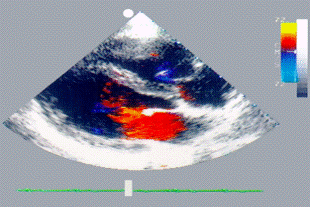

Рис. 21. Двухмерная цвентая допплер-эхокардиограмма больного с первичным дефектом межпредсердной перегородки: в области дефекта виден представленный красным цветом поток крови слева направо (шунт)